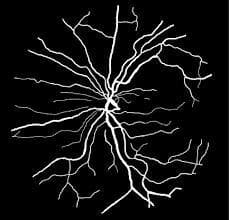

CHASE_DB1 is a dataset for retinal vessel segmentation which contains 28 color retina images with the size of 999×960 pixels which are collected from both left and right eyes of 14 school children. Each image is annotated by two independent human experts.

Source: MixModule: Mixed CNN Kernel Module for Medical Image Segmentation Image Source: https://www.mdpi.com/2073-8994/9/11/276